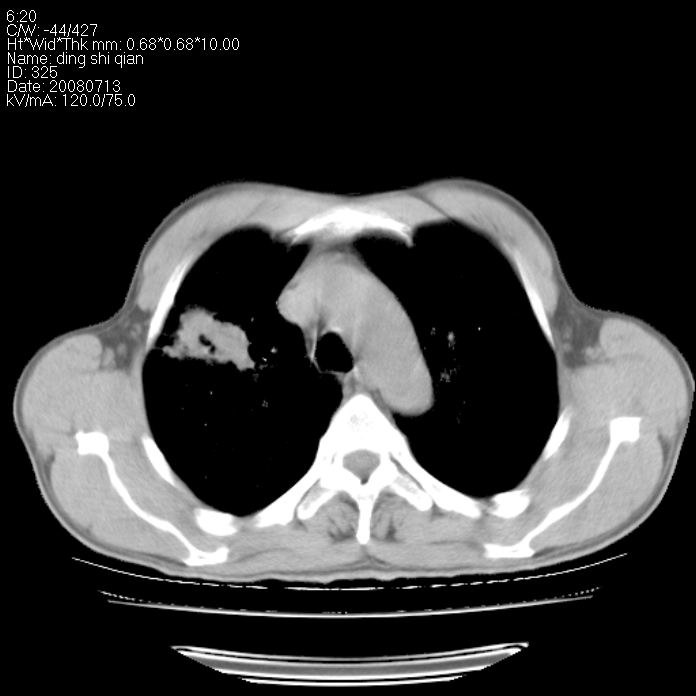

标题: CT14654:男 50岁 近来胸痛 [打印本页]

标题: CT14654:男 50岁 近来胸痛

右侧上肺块状软组织影,浅分叶,边缘毛刺证,与胸膜粘连,考虑:周围性肺癌

右侧上肺块状软组织影,浅分叶,边缘毛刺证,与胸膜粘连,考虑:周围性肺癌!支持!